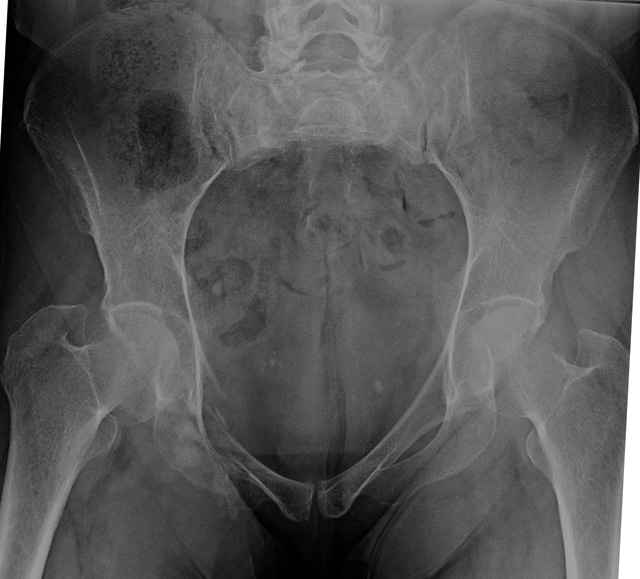

54 yo Female Fell c/o Pain

Initial Films

?Instability on Exam - Limited by Pain

NonOp Initial Mgmt

3 Months After Fall

Continued Pain & Immobility

(+) Instability to Compressive Manual Exam